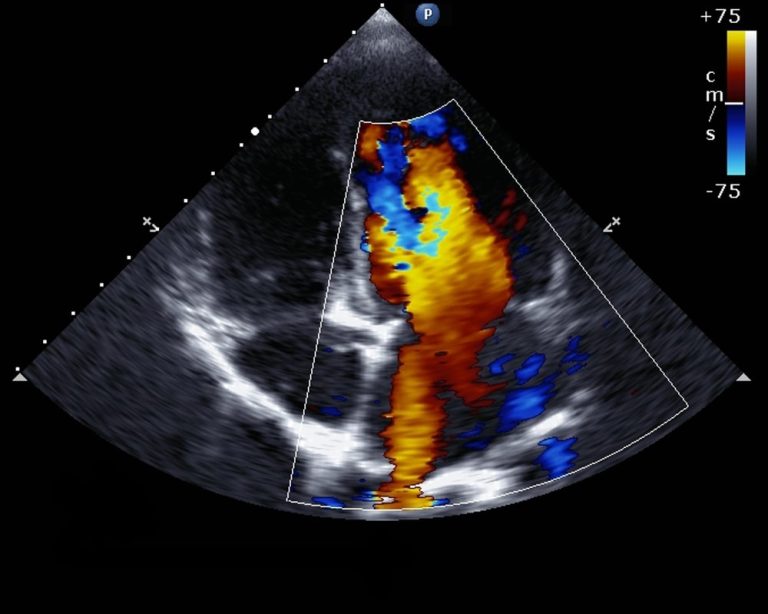

Transthoracic echocardiography (TTE) in Dubai at Emirates Hospitals Group. TTE is a non-invasive diagnostic imaging technique that uses ultrasound waves to create detailed images of the heart. It is one of the most commonly performed cardiac imaging tests and provides valuable information for both diagnosis and treatment planning.

1. Structural heart abnormalities: TTE allows for the assessment of the heart’s structure, including the chambers, valves, and major blood vessels. It can help diagnose various structural heart abnormalities such as valve diseases (e.g., mitral regurgitation, aortic stenosis), congenital heart defects, cardiomyopathies, and pericardial diseases.

3. Heart valve function: TTE can evaluate the function and integrity of heart valves, detecting conditions such as valve regurgitation (leakage) or stenosis (narrowing). It helps assess the severity of valve dysfunction, identify the affected valve(s), and guide treatment decisions.